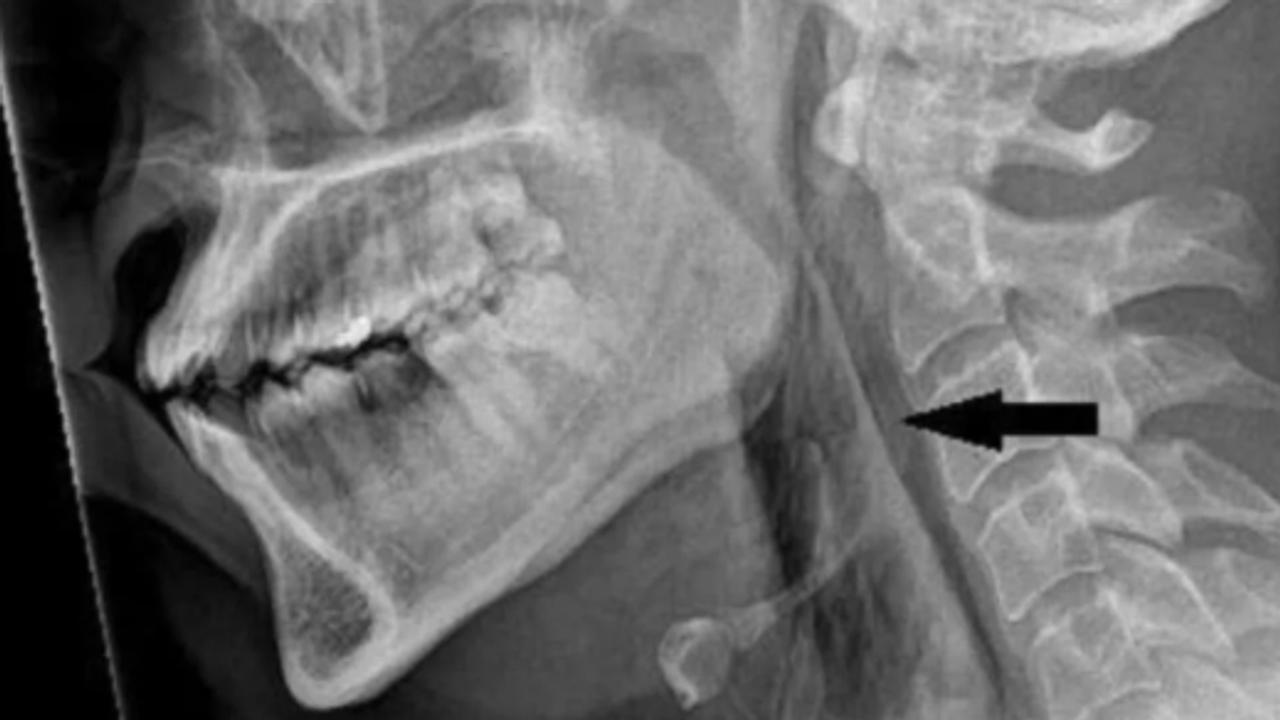

ಮನುಷ್ಯನಿಗೆ ಸರ್ಜಿಕಲ್ ಎಂಫಿಸೆಮಾ ಇದೆ ಎಂದು ಎಕ್ಸ್-ರೇ ಮೂಲಕ ತಿಳಿದುಬಂದಿದೆ. ಈ ಕಾಯಿಲೆಯು ಚರ್ಮದ ಆಳವಾದ ಅಂಗಾಂಶ ಪದರಗಳ ಹಿಂದೆ ಗಾಳಿಯು ಸಿಕ್ಕಿಹಾಕಿಕೊಳ್ಳುತ್ತದೆ. ಬಳಿಕ, CT ಸ್ಕ್ಯಾನ್ ಮಾಡಿದ ನಂತರ ಕುತ್ತಿಗೆಯ ಮೂರನೇ ಮತ್ತು ನಾಲ್ಕನೇ ಕಶೇರುಖಂಡಗಳ ನಡುವೆ ಹರಿದಿದೆ ಎಂದು ತೋರಿಸಿದೆ. ಹೆಚ್ಚುವರಿಯಾಗಿ, ಅವರ ಶ್ವಾಸಕೋಶ ಮತ್ತು ಎದೆಯ ನಡುವಿನ ಪ್ರದೇಶದಲ್ಲಿ ಗಾಳಿಯು ಸಂಗ್ರಹವಾಗಿತ್ತು.